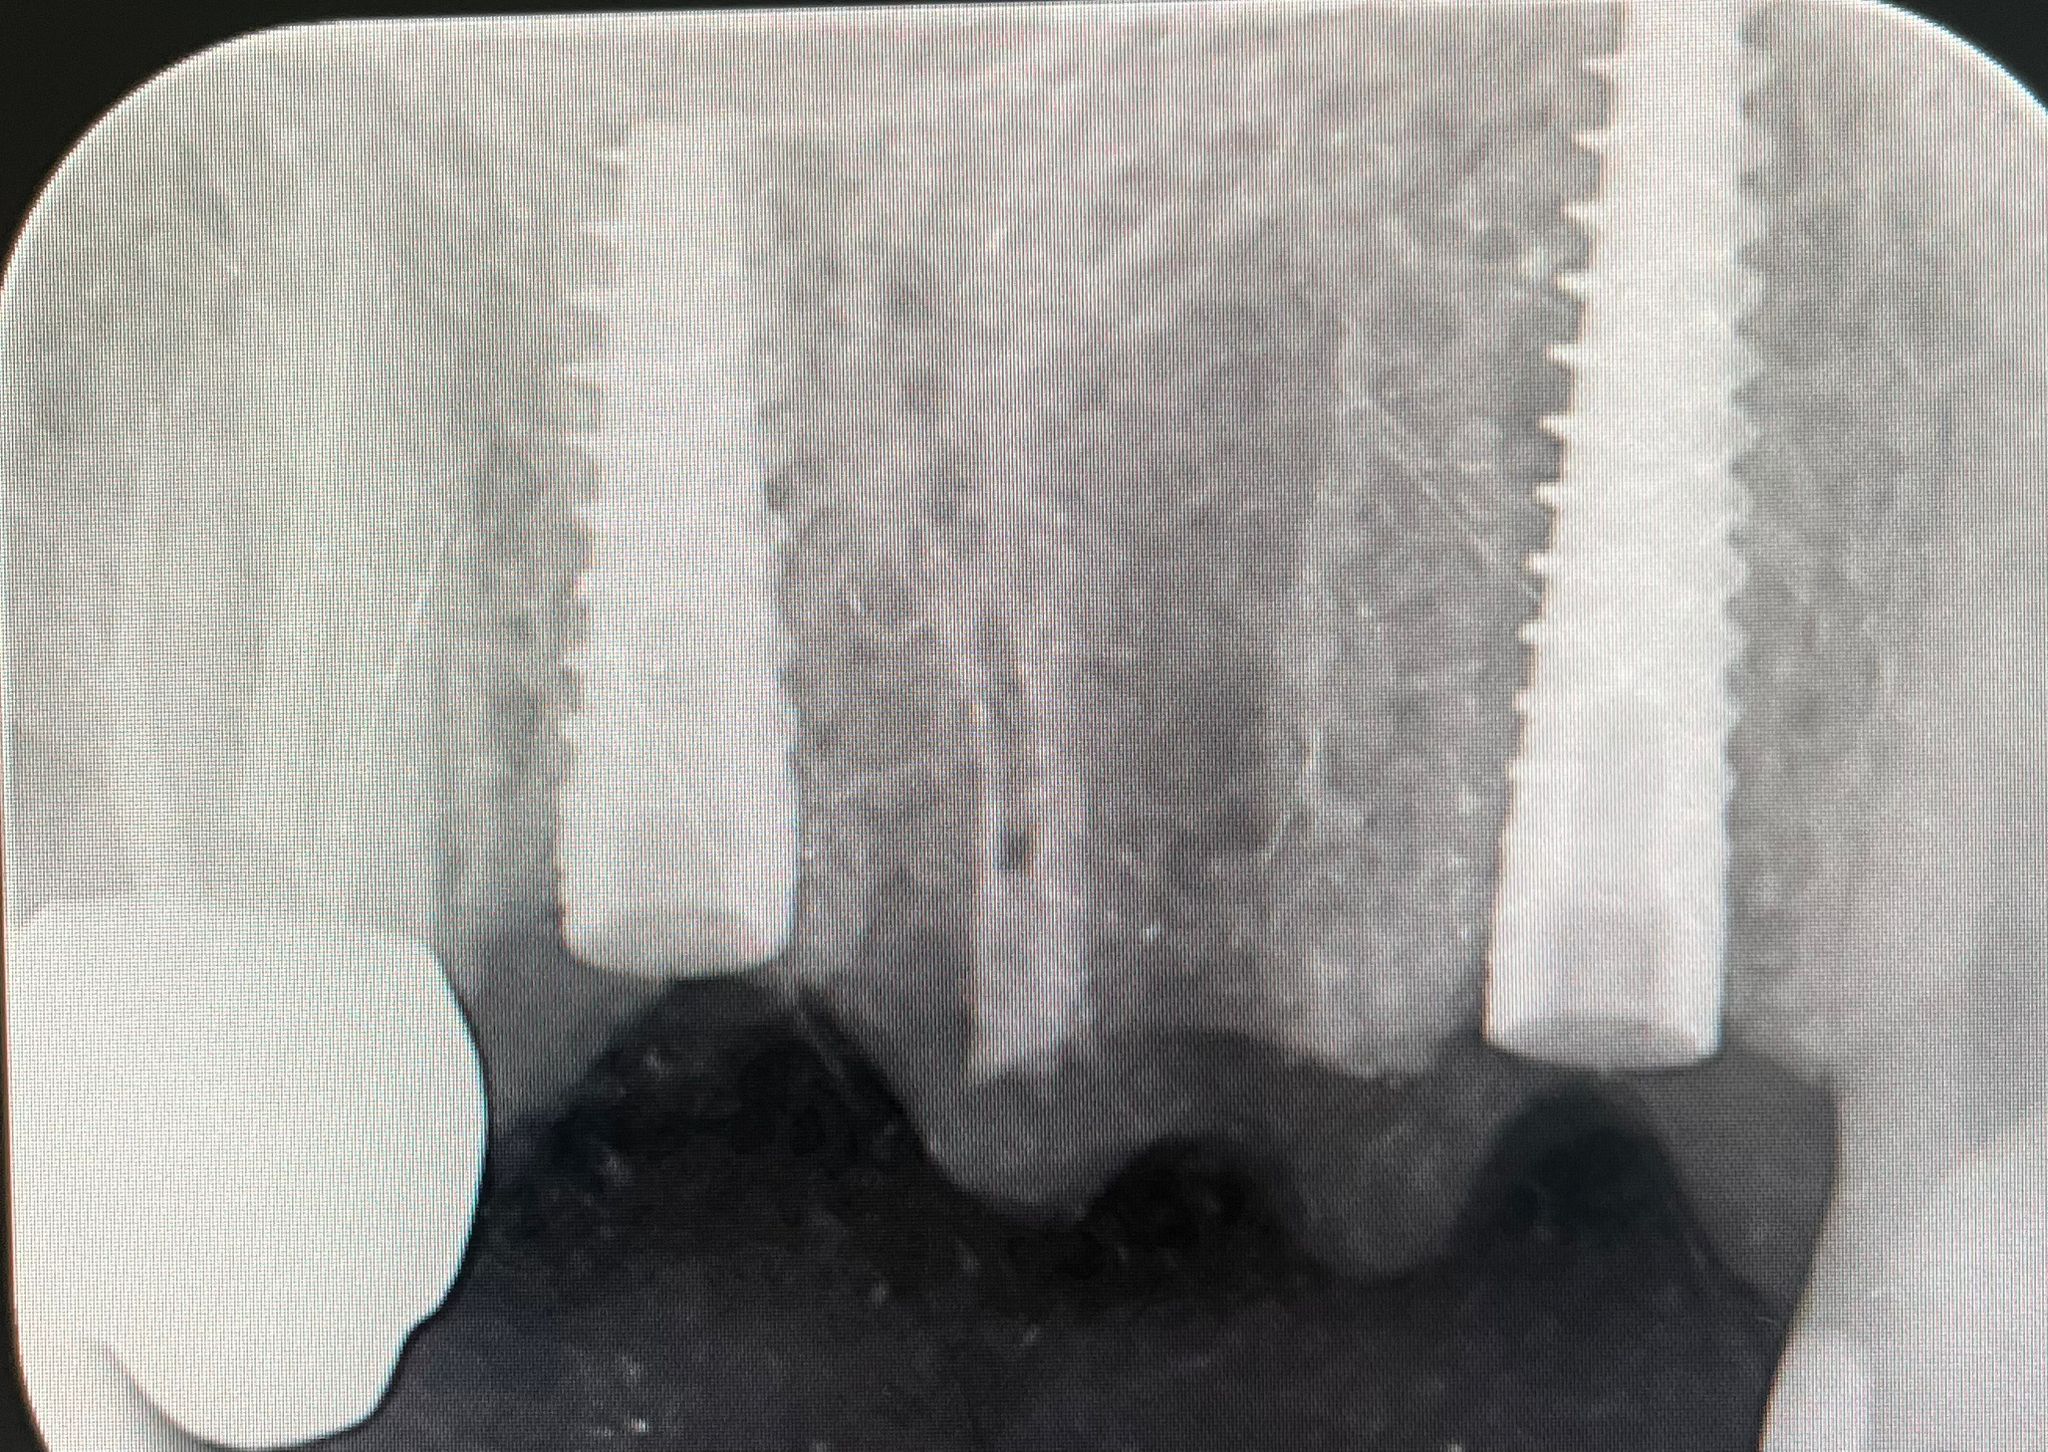

Presso lo Studio Dentistico Zambon siamo specializzati in trattamenti avanzati come il postestrattivo con carico immediato, un intervento innovativo che consente di sostituire i denti mancanti in modo rapido e sicuro, riducendo notevolmente il tempo di guarigione e il disagio per il paziente.

Grazie all’utilizzo della chirurgia guidata, siamo in grado di pianificare e realizzare impianti dentali con precisione, assicurando risultati eccellenti e duraturi.

Il trattamento postestrattivo con carico immediato è un protocollo che permette di inserire un impianto dentale subito dopo l’estrazione del dente naturale, evitando lunghi tempi di attesa tra l’estrazione e l’inserimento del nuovo dente. Questa soluzione si dimostra ideale per chi desidera ripristinare il sorriso e la funzionalità dei denti in tempi ridotti, evitando multiple sedute e massimizzando il comfort.

La chirurgia guidata è una tecnica avanzata che si avvale di tecnologie digitali per pianificare e simulare l’intervento in modo personalizzato. Con una scansione digitale 3D della bocca, il nostro team può posizionare gli impianti con estrema precisione, seguendo un percorso predefinito che riduce il margine d'errore. Questo approccio, unito al trattamento postestrattivo con carico immediato, offre diversi vantaggi: